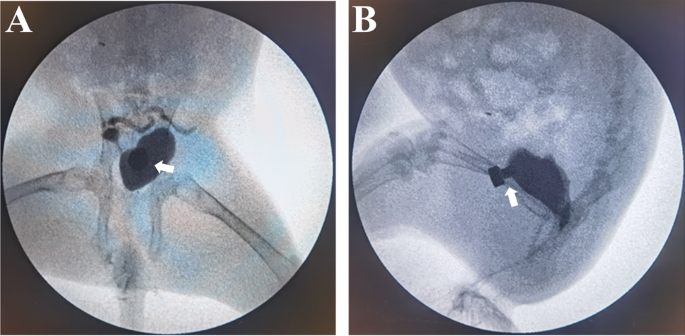

The daughter magnets were successfully inserted in the bladder in all animals, and the parent and daughter magnets were successfully attracted to each other. No gross hematuria was observed postoperatively. X-ray monitoring showed that the parent magnet and daughter magnet were attracted together (Fig. 3), and cystography showed that the magnets were in correct position (Fig. 4). The average operation time was 4.46 ± 0.75 min. All 12 rabbits survived with no postoperative complications such as bowel injury, hematuria, or wound infection. After a mean time of 10.08 ± 1.62 days after surgery, the magnets were detached from the abdominal wall, and the bladder fistula was formed. Necrotic bladder and abdominal wall tissues were seen between the detached daughter magnet and parent magnet (Fig. 5A). Macroscopic observation showed that the fistula was unobstructed (Fig. 5B–E), and the abdominal wall at the fistula was closely adhered to the bladder (Fig. 5F). There was no tissue adhesion in the pelvic cavity. Histological examination revealed a continuous and smooth mucosal surface at the junction of the abdominal wall with the bladder (Fig. 6).

Before the surgery, rabbits were reared in single cage for 1 week and provided ad libitum access to standard rabbit chow and water. The rabbits were anesthetized by intravenous injection of 3% pentobarbital sodium (1 mL/kg) via ear vein after weighing. When the loss of paw retraction reflex was confirmed, the animal was placed in the supine position on the operating table and the limbs were immobilized. The lower abdomen and perineum were shaved. The interventional guide wire (0.035 in; TERUMO, Japan) was inserted through the urethra into the bladder and confirmed by X-ray (Fig. 2A). The end of the guide wire was inserted into the central hole of the daughter magnet and the scalp needle tube (Fig. 2B). By pushing the scalp needle tube, the daughter magnet was pushed along the guide wire into the bladder (Fig. 2C). Subsequently, the guide wire was removed and the daughter magnet was left in the bladder (Fig. 2D). The parent magnet was placed over the abdominal wall above the pubis so that the daughter magnet in the bladder was attracted to it (Fig. 2E). The daughter magnet was placed in the bladder according to the requirements of aseptic operation. The attachment of the magnets was monitored under X-ray, and the position of the magnets was confirmed by cystography.